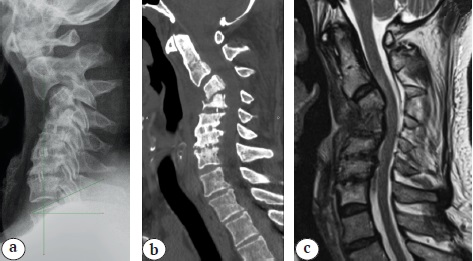

Considering the clinical picture and radiological findings, the patient underwent surgery in May 2021: anterior cervical discectomy, decompression of the spinal canal and interbody fusion at the C5-C6, C6-C7 levels (Fig. 2). Postoperative period was uneventful, and the radicular pain syndrome was partially resolved (intensity was up to 5 points according to VAS).

Fig. 2. MRI (a — T2 images; b — STIR images) and CT (c) after the first operation: two interbody implants (PEEK cages) are identified at the C5–С6, C6–С7, C4–С6 ossification of the posterior longitudinal ligament (segmental type according to the Committee on the Ossification of the Spinal Ligaments)

Six months after the initial surgery, the patient returned due to the persistence of clinical complaints. Clinical and instrumental examination was performed. The decision was made to perform a staged surgery consisting of anterior cervical discectomy, decompression of the spinal canal and spondylodesis of the C4-C5 segment.

Early postoperative period was complicated by the development of deep SSI, for which empiric antibacterial treatment (parenteral injection of vancomycin 1.0 twice a day for 3 weeks) was administered. Revision surgeries (necrectomy, abscessotomy, removal of interbody cages) were not performed. Cervical spine MRI in the setting of deep SSI (16 days after anterior cervical discectomy and C4-C5 spondylodesis) showed the presence of an epidural abscess and focal myelopathy at the C2-C3 level, a prevertebral abscess at the C2-C6 level and spondylitis at the C3-C5 level (Fig. 3).

Fig. 3. MRI after the second operation: a — STIR images; b — T2 images: prevertebral, epidural abscesses, C3–С5 spondylitis, focal myelopathy at C2–С3